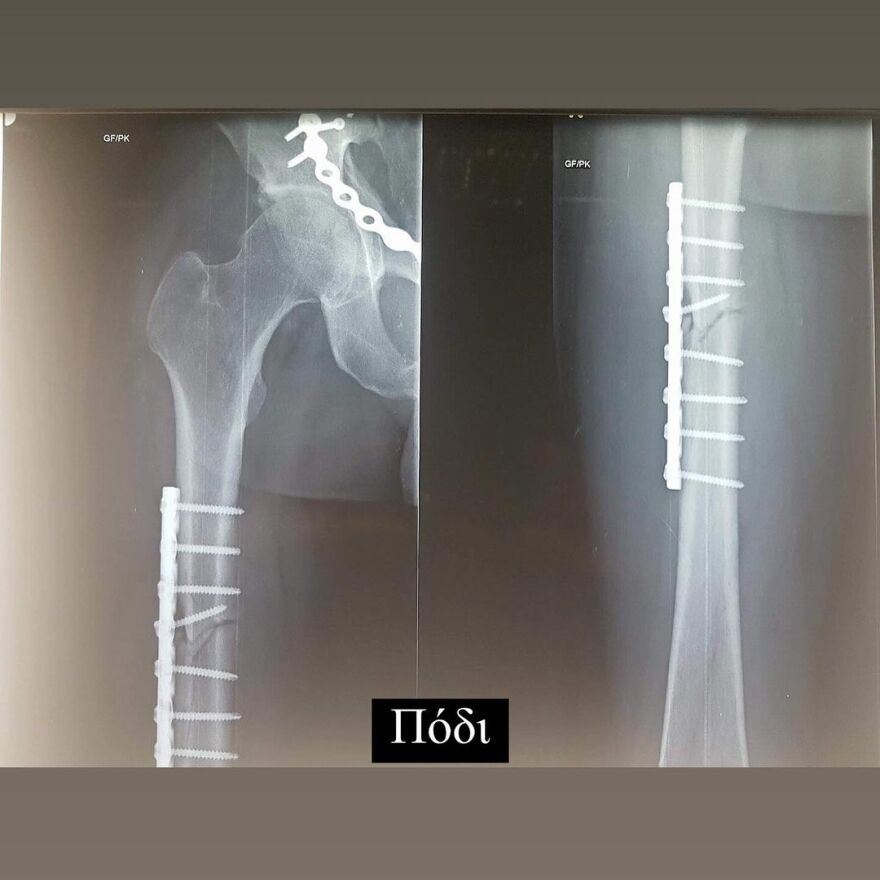

Έδειξε για πρώτη φορά τις ακτινογραφίες με τις λάμες, που έχουν τοποθετηθεί στο σώμα του μετά το ατύχημα

Σε ανάρτηση που έκανε στον προσωπικό του λογαριασμό στο Instagram, ο Ηλίας Βρεττός έδειξε στους διαδικτυακούς του φίλους τις λάμες που έχει στο σώμα του.

Συγκεκριμένα, δημοσίευσε μια σειρά από φωτογραφίες με τις ακτινογραφίες που έκανε. Σε αυτές φαίνονται οι λάμες στο χέρι, το πόδι και τη λεκάνη του.

Στη λεζάντα της ανάρτησής του έγραψε: «19/02 Αγία Φιλοθέη μου Μεγάλη η Χάρη σου!!! Σ´ευχαριστώ… 6 χρόνια πέρασαν και όλα ακόμα μοιάζουν σαν χθες… Τα σίδερα μέσα μου που για πρώτη φορα σας δείχνω στα X-rays έτσι κι αλλιώς δεν με αφήνουν να ξεχαστώ. Όμως είμαι καλά και κυρίως είμαι εδώ! Ο λόγος που το κάνω αυτό είναι γιατί κάθε χρόνο τέτοια μέρα με πιάνουν τα φιλοσοφικά μου και προσπαθώ να ξορκίσω το κακό».